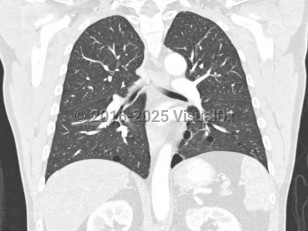

Approximately 80% of patients develop pulmonary cysts, which can be numerous and bilateral. They commonly affect the base of the lungs. They typically develop between the ages of 30 and 40 but have been described from ages 20-85. BHD patients are at 50-fold increased risk of spontaneous pneumothorax, with approximately 24% of those with pulmonary cysts developing spontaneous pneumothoraces at an average age of 38 years (range: 22-71 years). FLCN-mutation carriers have developed pneumothoraces as early as age 7.